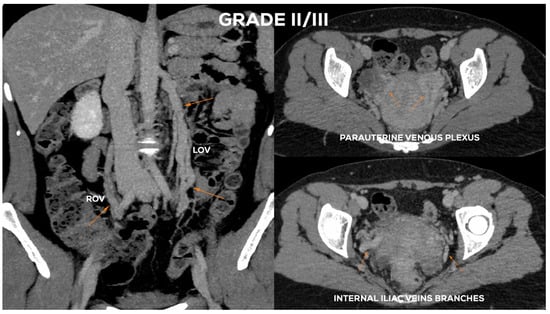

4.2.4. Grade II/III (GII/III)

| øLOV | incLOV | lPUV | bLIILV | øROV | incROV | rPUV | bRIILV | |

|---|---|---|---|---|---|---|---|---|

| GI | <6 | (−/+) | <5 | <5 | <5 | (−) | <5 | <5 |

| GI/II | 6–6.5 | (+) | <5.5 | <5.5 | <5 | (−) | <5 | <5 |

| GII | <7 | (+) | <6.5 | <6 | <5.5 | (−) | <5.5 | <5.5 |

| GII/III | 7.5–8 | (++) | <7 | <7 | <6 | (−/+) | <6.5 | <6 |

| GIII | >8 | (++) | 7–8 | <7.5 | <7.5 | (+/++) | <7 | <6.5 |

| GIV | >10 | (+++) | >8 | >8 | >8 | (+++) | >7.5 | >7 |